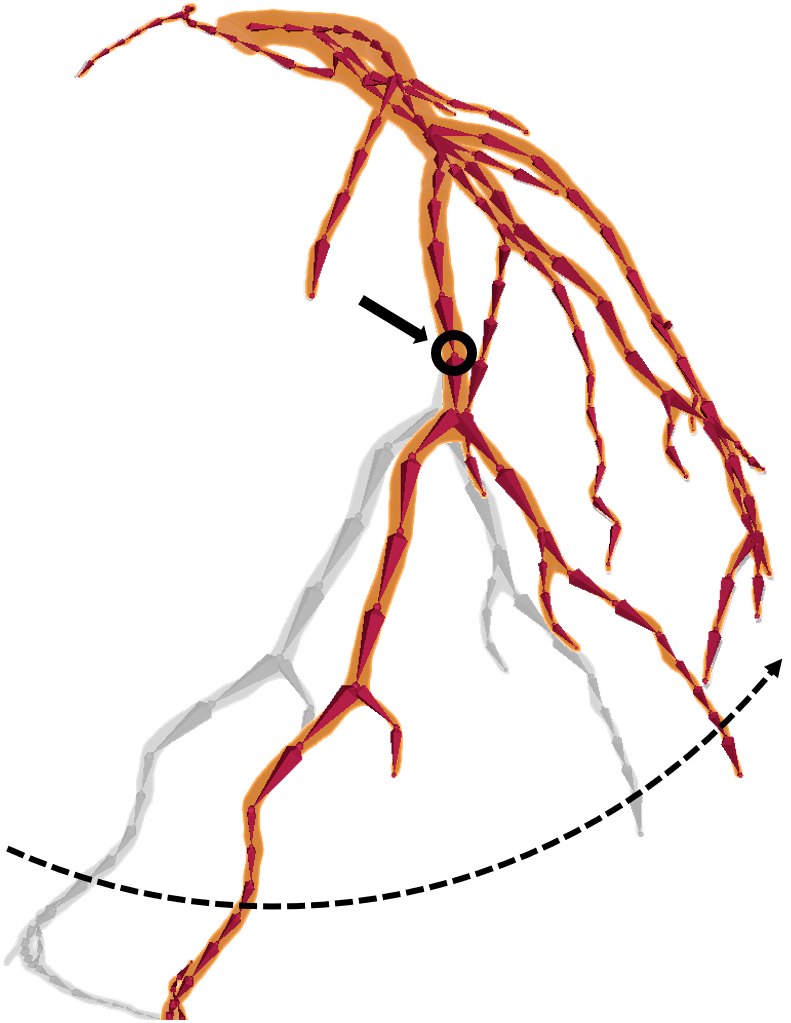

Figure 4: The alignment of a 3D coronary vessel tree model (panels (a), (c), and (e)) with the non-contrast CT scan (panels (b), (d), and (f)) based on rotations of subsequent Bones. The black solid arrows and circles in the 3D views (a), (c), and (e) indicate the center of rotation at a given alignment step. The rotation directions are shown using dashed curves. The corresponding contours of the LCA tree at a fixed slice of the CT scan are depicted in the axial views (b), (d), and (f).

Based on the newly created skeletal parameterization of the coronary vessel tree, the actual manual registration process can be carried out. This is done by iteratively rotating tips of the Bones to match the contours of the tree model with the vessels visible in the non-contrast CT scan based on an axial view555To display the axial slices of the CT scan together with the contours of the coronary vessel tree, we used the Cardiac Add-on for Blender, a specialized module for 3D geometric modeling of coronary arteries developed at Graylight Imaging (https://graylight-imaging.com/3d-modelling). However, the entire procedure of manual mesh-to-image registration can be realized using exclusively standard Blender’s tools, e.g., multiple Plane objects with textures corresponding to the axial slices of a CT scan, but it would be an even more time-consuming process., as shown in Fig. 4. The process starts by applying a rigid transformation of the initial vessel tree model to align its root with the ostium, which is usually clearly visible in a non-contrast CT scan. Subsequently, starting from the root of the tree, individual Bones are rotated as illustrated in Fig. 4. The deformations of the vessel tree are very intuitive since the child branches of the Bone being modified are rotated by the same angle, which is only a rigid transformation of the downstream part of the model. Once a part of the branch is no longer visible in the non-contrast scan, it is cut at that point, and all of its child branches are removed from the model.